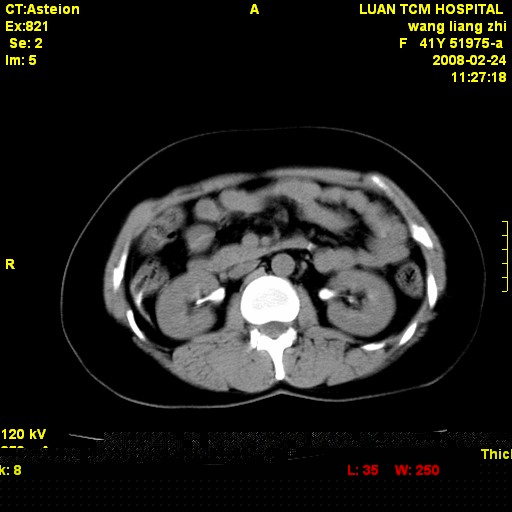

以下是引用dyqct在2009-8-23 16:17:00的发言:[br]考虑:1、造影剂进入腹腔、结肠旁沟、肝周;[br] 2、子宫明显增大(腺肌增生症?);[br] 3、膀胱显影是由于造影剂吸收后经肾分泌进入膀胱的;[br] 4、建议mri检查子宫。